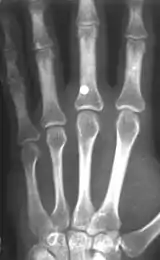

Иноро́дное те́ло (лат. corpus alienum) — с медицинской точки зрения любой чужеродный предмет, попавший внутрь организма. В узком смысле — посторонние предметы различных размеров, попавшие в глаз, ухо, нос, глотку, гортань, в пищевод или трахею (дыхательное горло). Инородное тело, даже не повредив окружающие ткани, может стать причиной смерти. Например, в результате удушья, вызванного рефлекторным спазмом голосовых связок или непрофессиональных попыток извлечения инородного тела, приведших к гибели пациента[1], а также в результате контакта со слизистой (например, батарейка может вызвать химический ожог[2]). Дети могут засунуть мелкие предметы, например бусины, в нос или ухо[3]